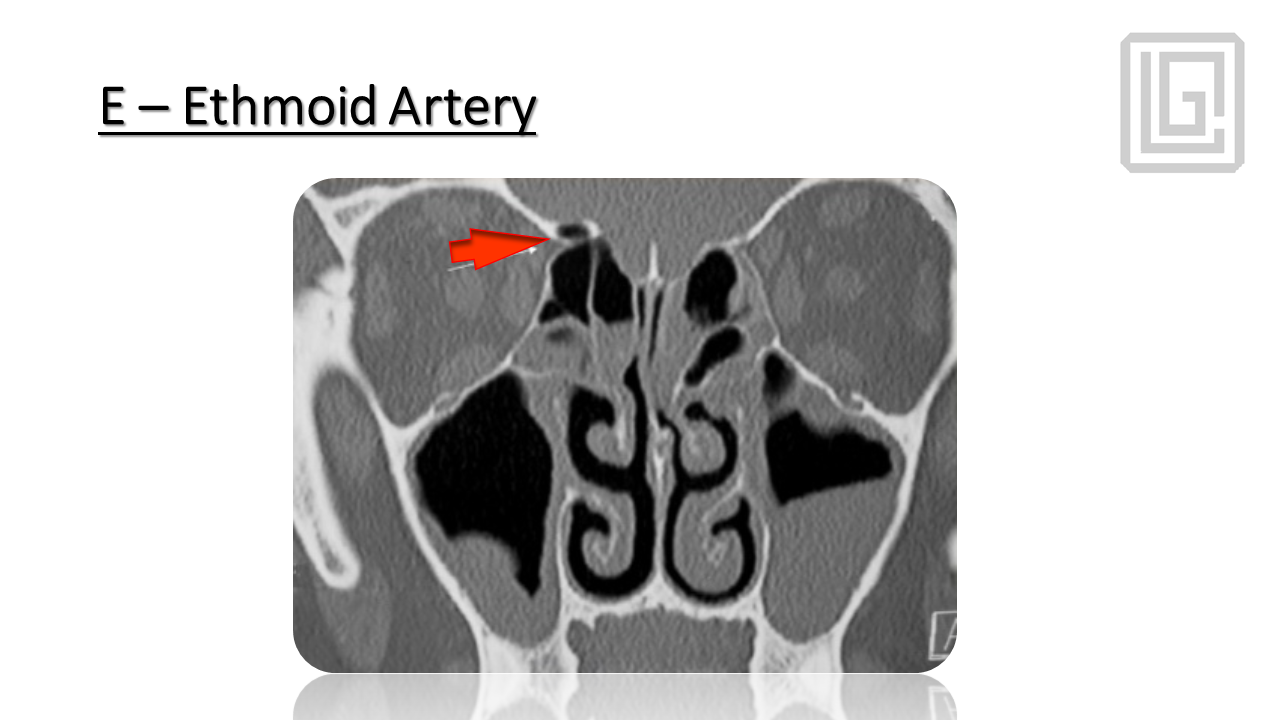

In-depth presentation on the pathophysiology of chronic rhinosinusitis, radiologic planning, sinonasal anatomy, and step-by-step FESS surgical protocol. Covers infundibulum, osteomeatal complex, surgical landmarks, instrumentation, complications, and postoperative management. Presented by Dr. Levon Galstyan.